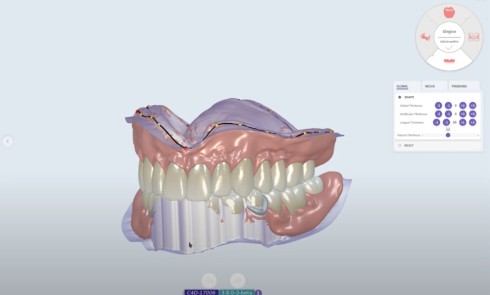

Avec l’essor de la CFAO (Conception et Fabrication Assistées par Ordinateur) et le développement de blocs en composite usinable, il semble intéressant d’en faire usage chez nos jeunes patients. Le but de cet article est de montrer dans quelle mesure la CFAO directe peut s’intégrer au quotidien en odontologie pédiatrique.

Pour cela, dans un premier temps, nous présenterons : le matériel, les indications et le protocole, à l’aide de deux cas cliniques. Dans un second temps, nous récapitulerons les avantages…